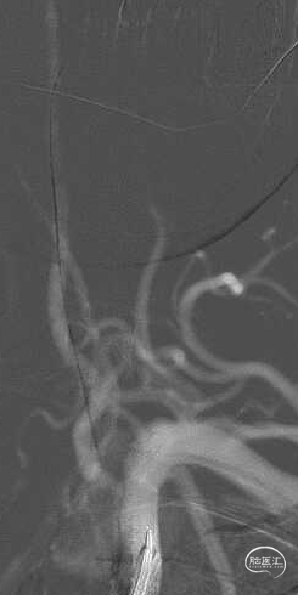

右侧椎动脉造影提示左侧锁骨下动脉盗血,左侧锁骨下动脉闭塞,近端残端较圆钝。

8F Guiding+5F MPA同轴置于左侧锁骨下动脉残端处,反复尝试Command 190cm及Command ES 190cm导丝配合Rebar-18微导管,导丝无法进入真腔,更换Connect 195cm导丝尝试后顺利进入真腔,使用小球囊预扩, Guiding跟到病变远端。

更换Supracore导丝,使用雅培 5*40mm Armada35 球囊扩张后在闭塞起始部植入8*29mm Omnilink支架。

使用雅培 Command导丝顺利超选进入左椎V2段,冠脉3.0*12mm球囊进行扩张,在V18导丝的支撑下,在左侧椎动脉起始部植入一枚雅培4.5*15mm Herculink支架。支架植入后,造影提示椎动脉狭窄得到明显改善。